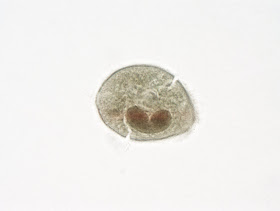

The following objects were seen on a stool ova and parasite examination from a patient with diarrhea and abdominal pain. They measure approximately 80 micrometers in greatest dimension. Identification? What feature makes this parasite unique?

1. Balantidium coli- the only ciliate protozoan that parasitizes humans

2. Balantidium coli and it's the only ciliate that infects humans.